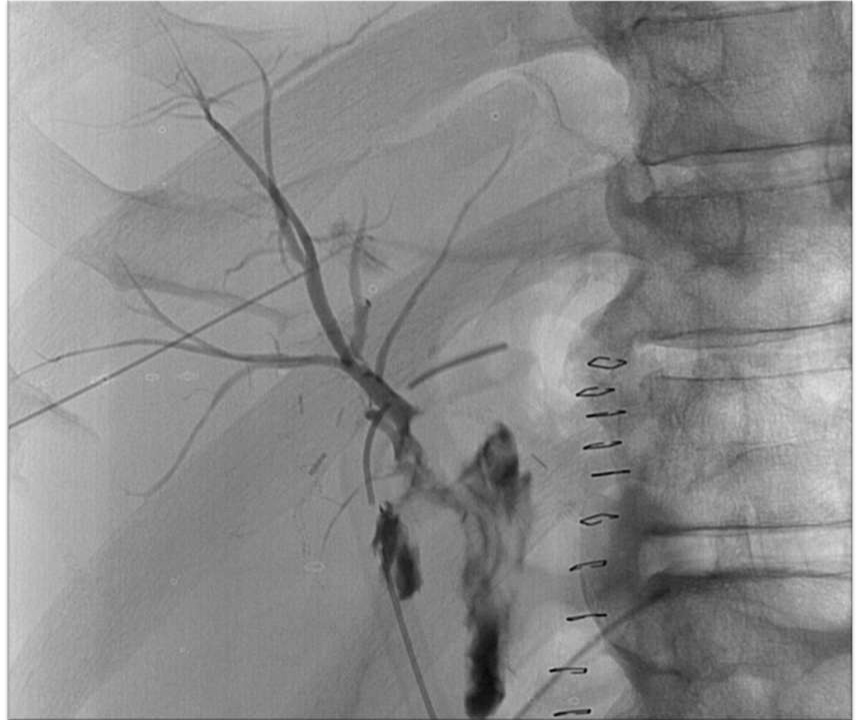

58岁男性 四段肝癌, 左半肝切除术,肝胆管空肠吻合术 术后第七天,肝下引流管持续大量胆汁流出,怀疑胆肠吻合口漏,胆红素正常

58岁男性

四段肝癌,

左半肝切除术,肝胆管空肠吻合术

术后第七天,肝下引流管持续大量胆汁流出,怀疑胆肠吻合口漏,胆红素正常

PTC: Patent HJ anastomosis, no leak

PTC: Obstructed right posterior hepatic duc

PTC: Obstructed right posterior hepatic duct

Biliary drains inserted in RAHD & RPHD Plan: Surgical revision

But: AMI, surgery deferred